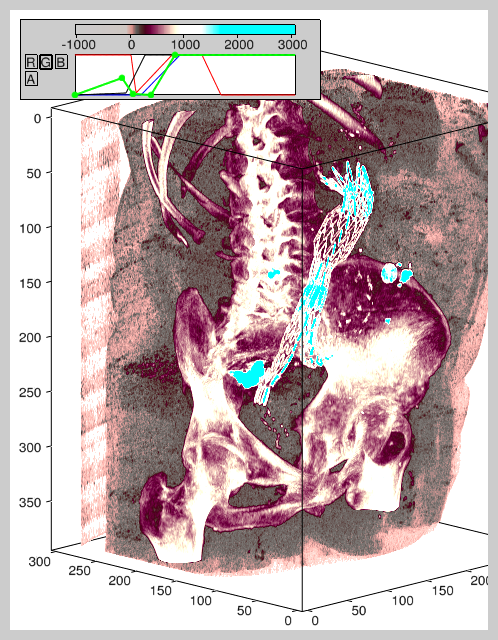

Here's an image of a stent graft visualized using the raycast render program. Contrast fluid was injected in the bloodstream during acquisition of the CT scan, which enables distinguishing it from the surrounding tissue:

Here's another stent, also showing the pelvic bone (using the MIP renderer):